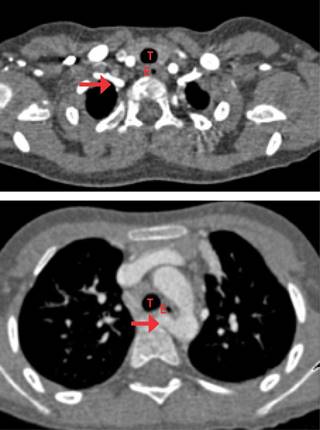

Estudios: difusión de monóxido de carbono (DLCO) 7.5 mL/min/mmHg (valor predicho 10.2), espirometría posbroncodilatador con una respuesta en volumen espiratorio forzado en el primer segundo (FEV1) del 16% y de más de 200 mL. La radiografía de tórax muestra un patrón atelectásico (Figura 1). Serie esofagogastroduodenal (SEGD) con presencia de reflujo grado III; en la angiotomografía de tórax (angio-TC) se observa una subclavia derecha aberrante (Figura 2), lo mismo que en la aorta descendente, también un vaso aberrante (Figuras 3 y 4).

Figura 2: Angiotomografía computarizada de tórax fase arterial: se observa la presencia de subclavia derecha aberrante (flecha) que discurre desde la cara posterior de porción proximal de aorta descendente hacia la derecha del paciente por detrás del esófago (E) y que reduce el calibre del mismo en forma considerable.